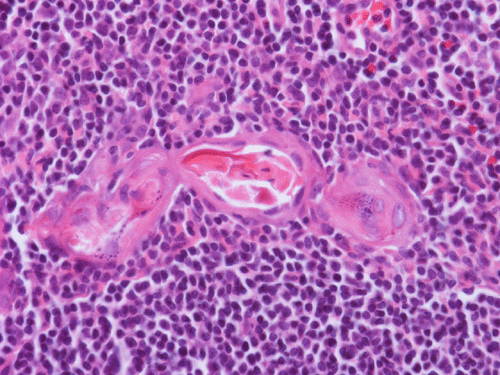

Clinical information: The patient is a 36 year-old woman who presented with a 2 cm swelling in the left side of her neck. The mass was not tender, warm, or painful. The overlying skin was unremarkable. A CT scan was performed and showed a 1.8 x 1.2 cm relatively non-enhancing lesion within the carotid sheath displacing the carotid artery anterioriorly. The clinical and imaging features yielded an empirical diagnosis of an enlarged lymph node. The patient had no history of lymphoma, leukemia, or head and neck tumor. The mass was removed surgically in its entirety and was 2.5 cm in maximum dimension, well encapsulated, located at the level of the carotid bifurcation just lateral to the carotid artery and superiorly extending almost up to the level of the tonsils. The mass did not appear to be in continuity with the jugular vein or the carotid artery. It was not a part of the vagus nerve or sympathetic chain. The followings are representative images.